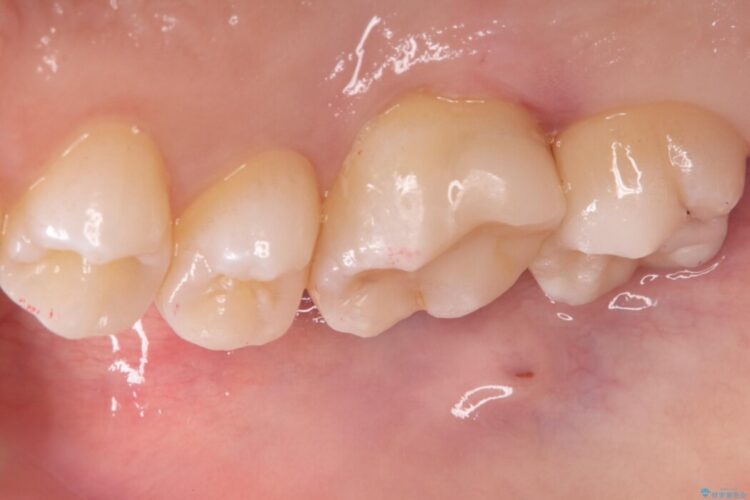

右上奥歯が欠けてしまい来院されました。

右上6番の舌側が欠けてしまっている状態でした。

破折リスクを考慮し、セラミックアンレーで治療を行うこととしました。